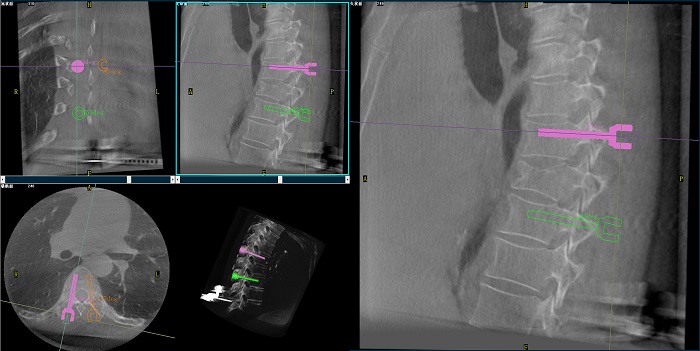

②機器人輔助胸椎手術操作難點之路徑規劃

人體胸椎的椎弓根較腰椎更狹窄,周圍有重要的神經和血管,選擇合適尺寸和長度的螺釘至關重要。螺釘過粗可能損傷椎弓根,過細容易發生形變,固定強度不夠;螺釘過長可能穿透椎體前緣,造成損傷,過短則固定不牢。

普愛醫療手術導航定位系統解決方案

使用機器人輔助手術,醫生不僅可以在影像的引導下,一次性完成多枚螺釘的路徑規劃,提高手術效率,而且可以精確地選擇螺釘的角度、直徑和長度,提高手術的成功率。